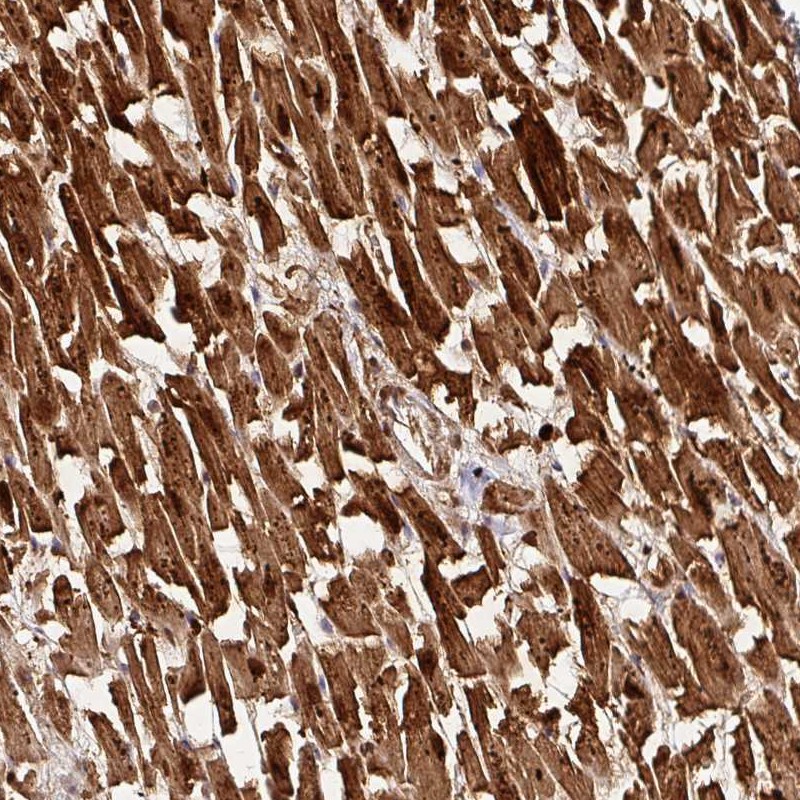

Immunohistochemical staining of human heart muscle shows strong cytoplasmic and nuclear positivity in myocytes.